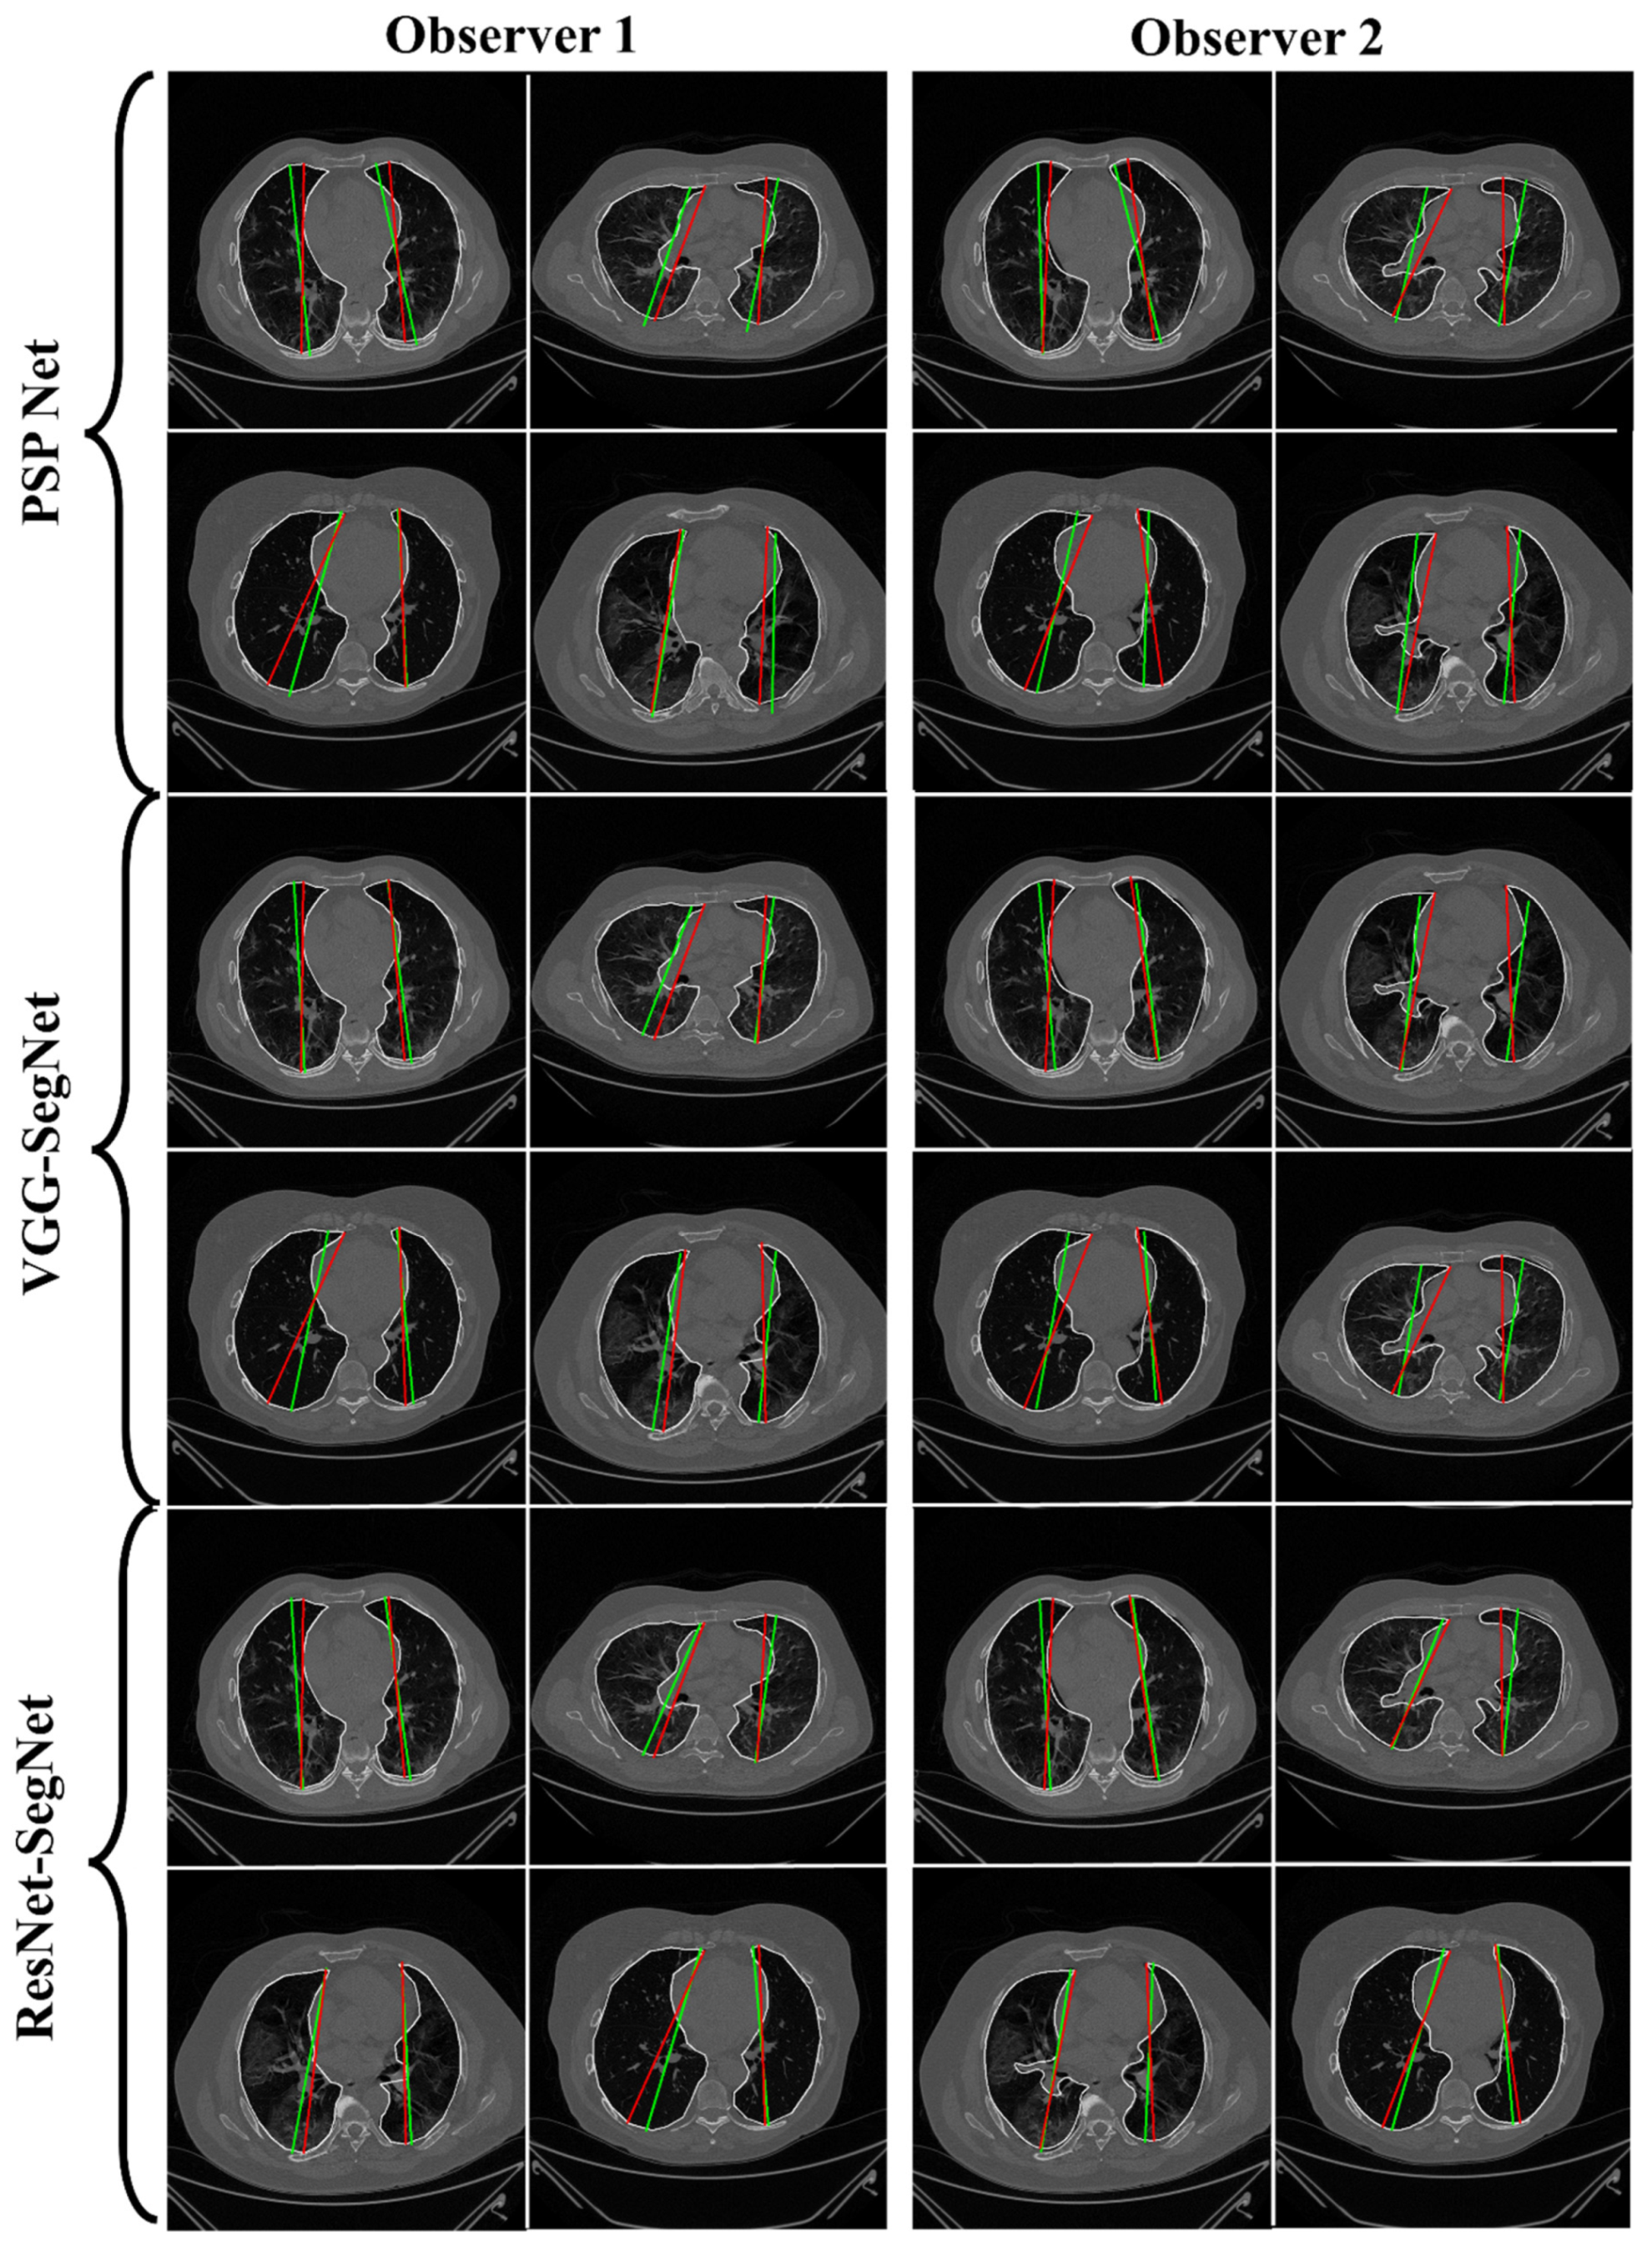

4.2.1. Lung Boundary and Long Axis Visualization